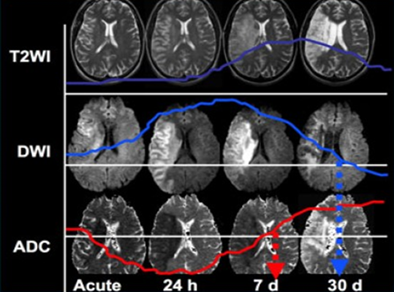

Chụp cộng hưởng từ (MRI):

Cộng hưởng từ là kỹ thuật nhằm phát hiện ra những bất thường về nhiều cơ quan trong cơ thể.

Tầm soát u não – đột quỵ não

Hình 14. Hình ảnh MRI não